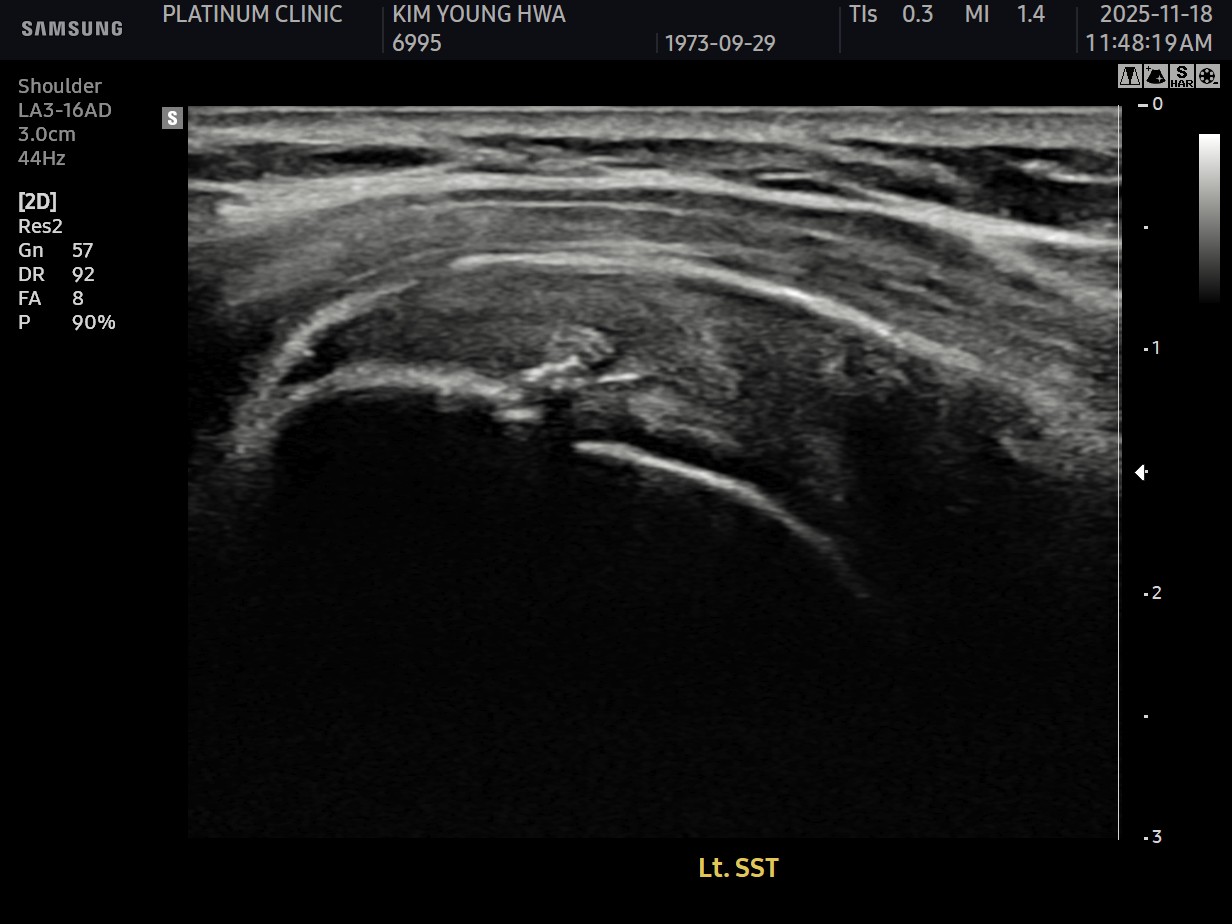

진단 결과:

- ✓관절면측 부분파열: 약 35%

- ✓근육 위축이나 지방 변성은 없음 (젊은 나이)

시술 과정

시술 시간: 약 35분

10주 후 초음파:

봉합 부위가 정상 인대처럼 하얗게 재생되어 있었습니다. 골수자극의 효과로 예상보다 빠른 재생이 확인되었습니다.

12주 후: PT 레슨 복귀. 처음에는 상체 운동 시범은 자제.

4개월 후: 벤치프레스 70kg 성공. 이전 무게의 약 80% 회복.

6개월 후: 이전 수준 완전 복귀.